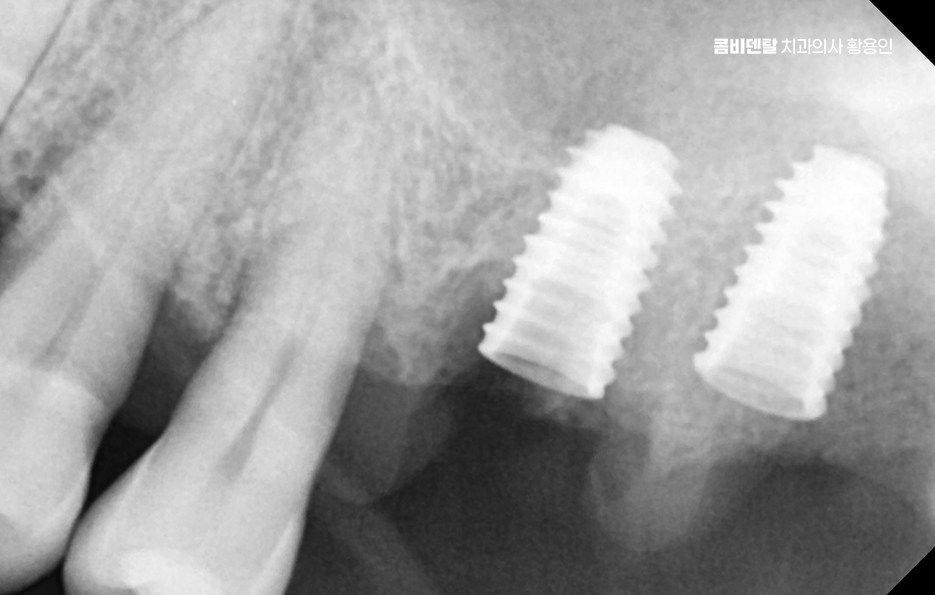

현재 기준으로 보면, 65세 이상이라면 평생 최대 2개까지 건강보험 적용으로 임플란트 치료를 받을 수 있으며 건강보험 자격에 따라 본인부담금이 다르긴 한데요, 일반 건강보험 가입자라면 본인부담금 30% , 차상위나 기초수급자라면 본인부담금 10~20% 수준까지도 혜택을 받을 수 있어요.

고령층에서 임플란트를 선택할 때 걱정하는 부분이 수술 자체이기도 한데 나이가 들면 뼈가 약해지고 당뇨, 고혈압, 골다공증 같은 전신질환을 겪고 있는 분들도 많다는 점에서 어르신 임플란트 지원 자체에 대해서도 혜택을 잘 받는 것이 중요하지만 노인 임플란트의 경우 현재 잇몸 뼈의 상태 뿐 아니라 전신건강에 대한 부분도 잘 체크해야 할 필요가 있는데요

그 뿐 아니라 예를 들어, 잇몸뼈가 너무 많이 녹아 있는 경우에는 뼈이식이나 상악동 거상술 같은 부가적인 치료가 필요한 경우도 많기 때문에 경험 많은 의료진과 치료 과정을 함께하는 것이 중요하며 장기적으로도 오래 함께할 치과를 잘 판단하실 필요가 있어요